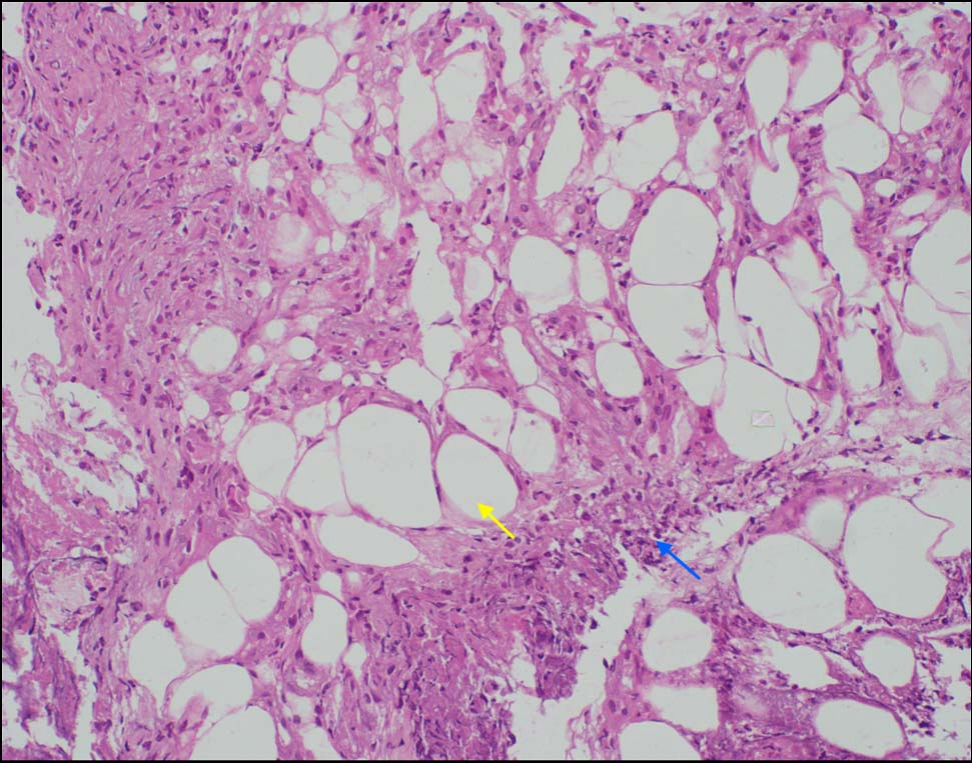

与本病相关的常见实验室异常包括C反应蛋白和脂肪酶升高,本例患儿均存在。组织病理学检查结合胰腺受累的背景证据可确诊胰腺性脂膜炎。Ball等提出胰腺性脂膜炎可能以间隔性脂膜炎起病,后期才发展为小叶受累。主要特征为小叶性脂膜炎,即以脂肪小叶为中心的炎症区域。另一特征为存在“鬼影细胞”,即脂肪细胞失去细胞核,转变为内含细颗粒物质的蓝灰色胞浆,呈厚壁样外观。本例患儿主要为间隔性脂膜炎(图3),伴小叶性脂膜炎灶。

图3 组织病理学显示脂肪细胞(黄色箭头),主要表现为间隔性脂膜炎,其特征为脂肪细胞周围的纤维间隔内有炎性浸润物沉积(蓝色箭头)